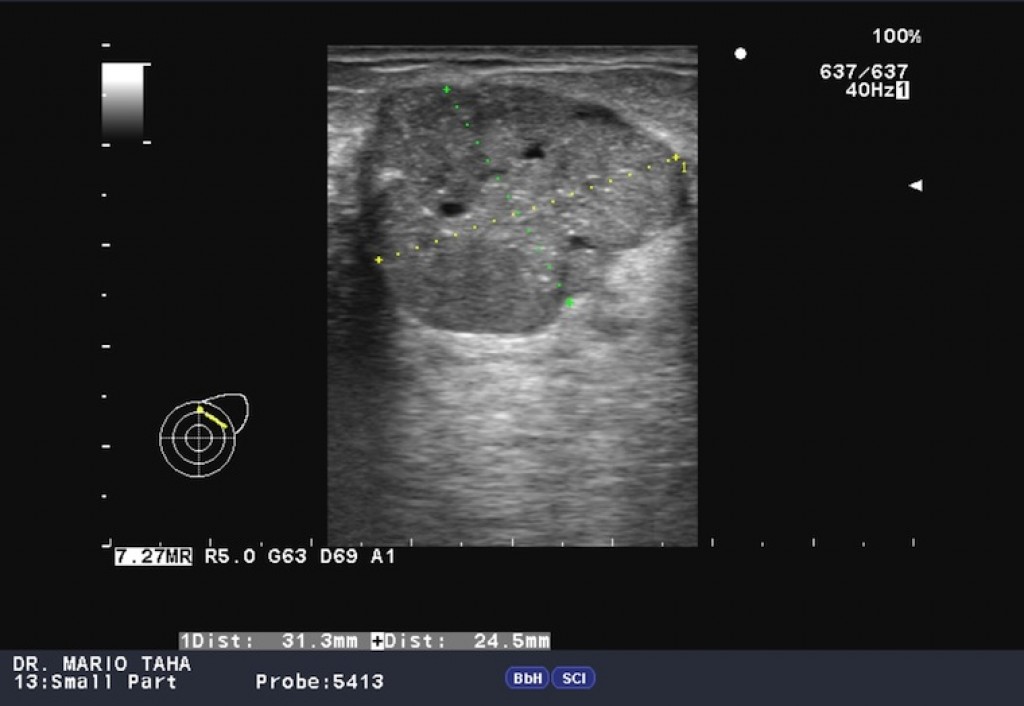

Ultrasound signs of a phyllodes fibroadenoma:

• An iso- or hypoechoic mass;

• Heterogeneous structure, with non-echoic inclusions in the event of large mass size;

• Rounded or oval in shape, with clear, even contours;

• Presence of acoustic effects (symmetrical lateral shadows, dorsal signal amplification);

• Significant intranodular vascularisation in CDI and PD modes;

• Strain-ratio index at elastometry is above 2.5.

A phyllodes breast tumor is shown below on ultrasound images. Author of photos No. 1 and No. 2: Mario Taha. Source: Radiopaedia [10]. Author of photo No. 3: Giorgio M. Baratelli. Source: Radiopaedia [10].